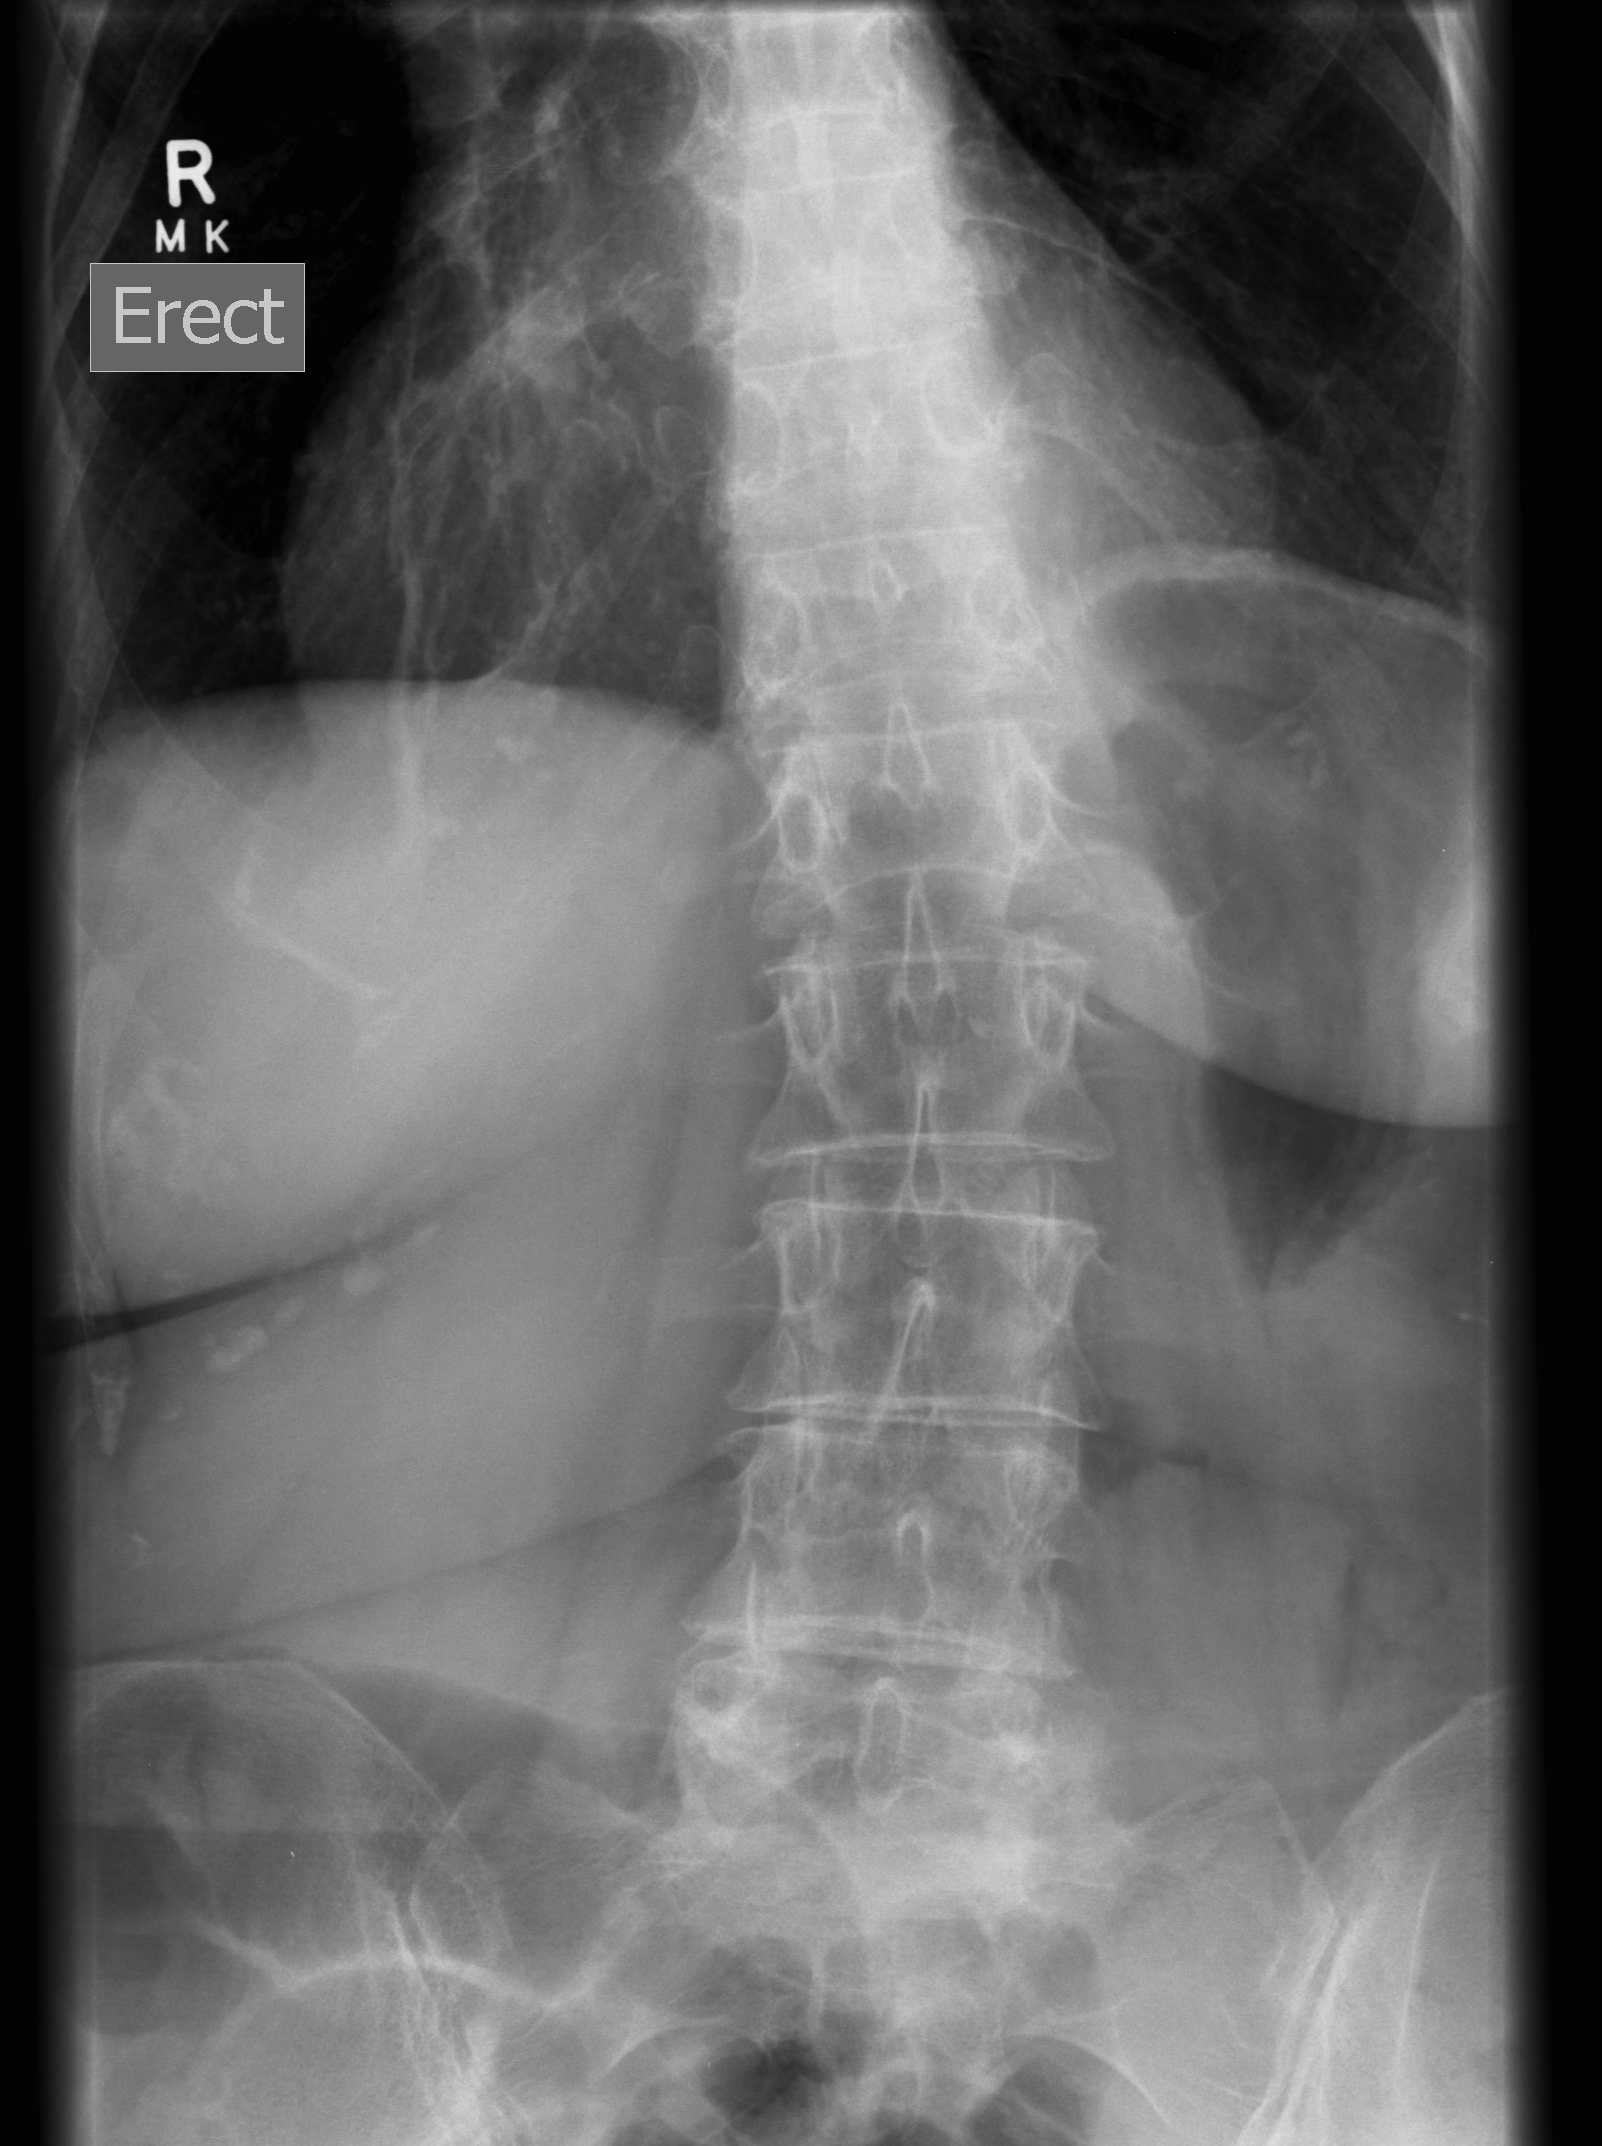

1. Abnormal gait / risk of falls

2. Lower back pain / scoliosis

3. Nerve palsy

- sciatic nerve - tolerate average 4.4cm lengthening

- common peroneal nerve - tolerate average 2.7 cm lengthening